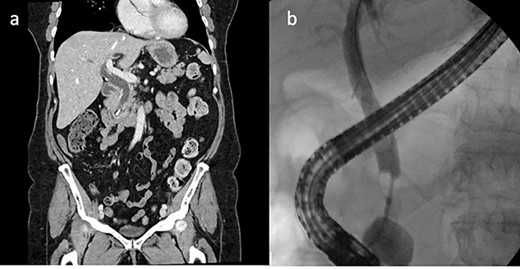

On examination, she was febrile at 38.1, abdomen was soft with epigastric tenderness and negative murphy’s sign. Laboratory investigations showed markedly deranged LFTs indicating a cholestasis pattern: aspartate aminotransferase (AST)—63 (10–35), alanine aminotransferase (ALT)—102 (5–30), alkaline phosphatase (ALP)—872 (30–115) and GGT—987 (5–35). Computed tomography (CT) abdomen showed a linear high density focus consistent with a 10-mm surgical clip obstructing the distal CBD, which was significantly dilated proximally (Fig. 1) two attempts were made to remove the surgical clips via ERCP and balloon extraction however the clip and stone remained impacted above the ampulla, which was quite edematous. After each unsuccessful attempt the bile duct was re-stented to allow biliary drainage and she was placed on antibiotic therapy to reduce the infection and resultant inflammation.

CT abdomen and ERCP. (a) CT abdomen showed a linear high density focus consistent with a 10-mm surgical clip obstructing the distal CBD, which was significantly dilated proximally (coronal). (b) ERCP showing filling defect in CBD.